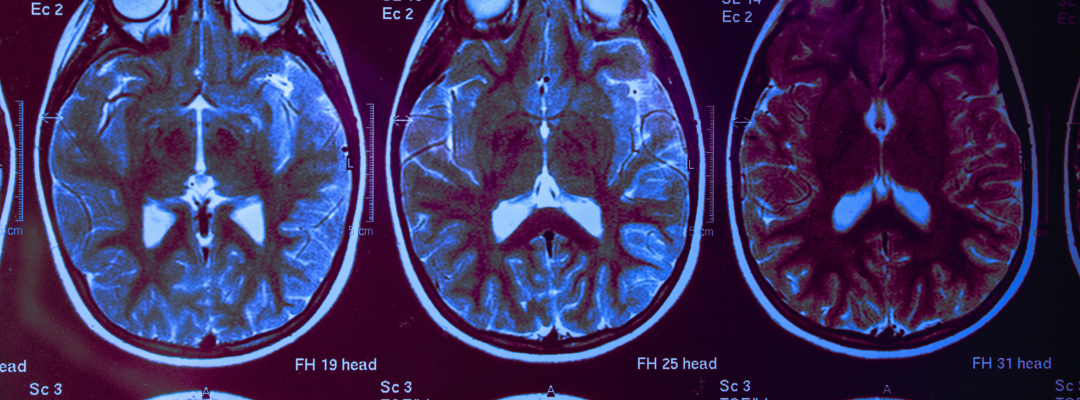

The claustrum is a structure of the brain that has been associated with consciousness and spirituality. In the mystical context, the claustrum is said to secrete a sacred oil known as "Christos" or "Christ." This oil is considered a spiritual essence related to the cerebrospinal fluid.

The mystical process describes how the claustrum releases a biochemical signal that activates the pineal and pituitary glands. These glands, in turn, secrete substances known as "milk and honey" into the cerebrospinal fluid. This sacred fluid descends through the spine and then ascends, carrying with it a spiritual energy that is said to purify and elevate consciousness.

The pituitary and pineal glands are essential for hormonal balance and circadian rhythms in the body. The pituitary gland, also known as the hypophysis, regulates various hormonal functions and is sensitive to environmental stimuli. The pineal gland, on the other hand, is known for its role in regulating sleep and producing melatonin.